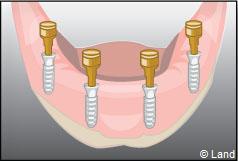

Exemple d’une réhabilitation complète implantaire

Situation clinique terminée